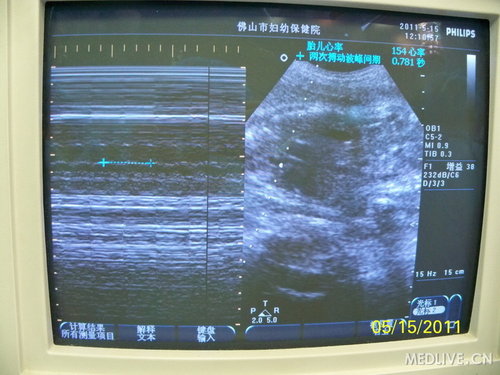

术中胎儿生命体征,SPO2约60-80%,心率135-155之间。

http://webres.medlive.cn/upload/000/016/708

B超监护下的胎儿心率、羊水深度

http://webres.medlive.cn/upload/000/016/713